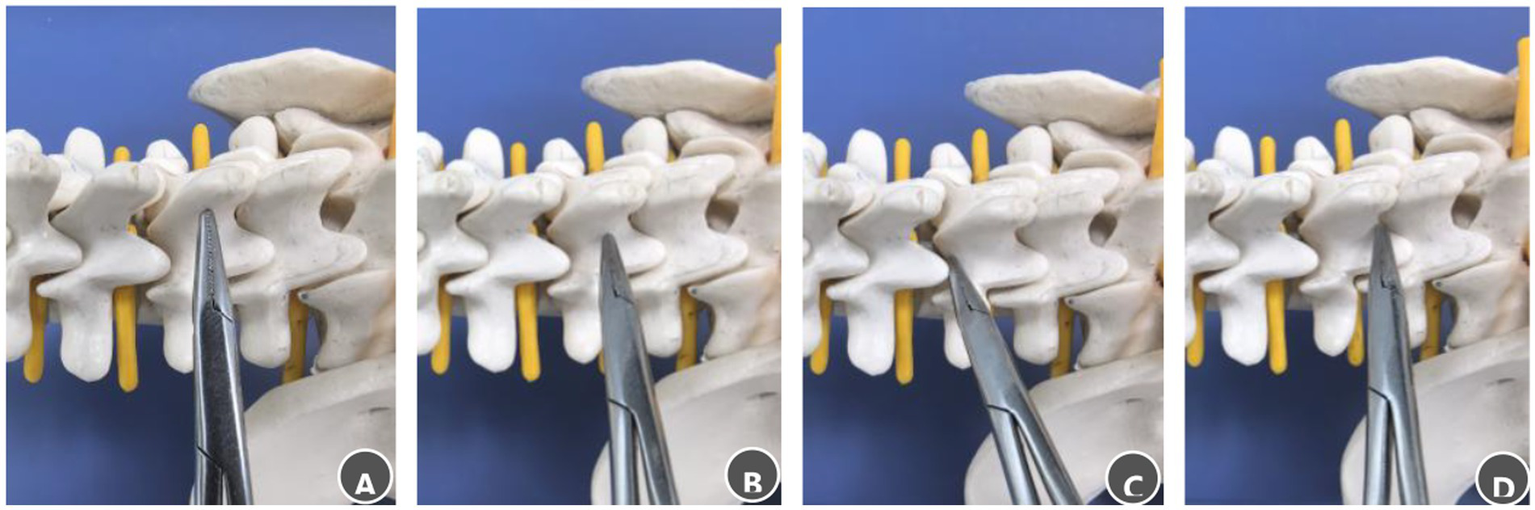

The initial skin incision was planned using lateral fluoroscopy with a C-arm. A longitudinal incision (1.8–2.0 cm in length) was marked 1.5 cm lateral to the midline on the side of the tumor mass, corresponding to the surface projection of the vertebral body or disc space adjacent to the tumor. A 6–8 mm initial skin incision was made at the center of this line. Through this incision, a clamp was introduced and directed medially to palpate the spinous process. The instrument tip was advanced inferiorly to the spinous process–lamina junction. It was then moved cephalad to locate the M-point (characterized by a subtle loss of resistance at the superior lamina edge) or caudally to identify the S-point (a similar sensation at the inferior edge) (Figure 3). The incision was then fully extended according to the spatial relationship between the identified landmark and the tumor. If the landmark corresponded to the tumor midpoint, the incision was extended symmetrically. If it aligned with a tumor pole, the landmark was positioned at the corresponding cranial or caudal end of the incision. The tubular retractor was then inserted along the final incision to ensure the tumor was centered within the operative field.

Steps for palpating bony landmarks in the posterior lumbar spinal canal. (A) Advance the clamp tip medially along the lumbar spinous process to locate the midline. (B) Slide the clamp tip caudally along the spinous process to the spinous process–lamina junction. (C) Move the clamp tip cephalad along the junction between the spinous process root and the lamina, a distinct loss of resistance indicates the M-point. (D) Move the clamp tip caudally along the same junction; a distinct loss of resistance indicates the S-point.